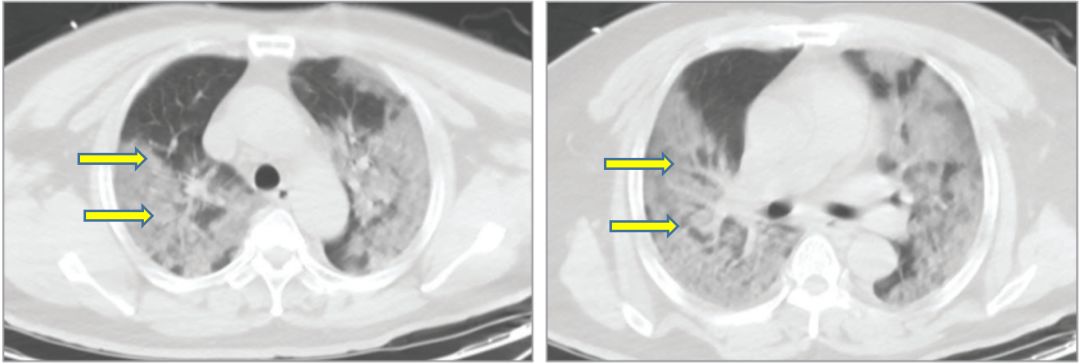

新冠肺炎肺部纤维化

新冠肺炎主要引起深部气道和肺泡损伤为特征的炎性反应,肺部纤维化及